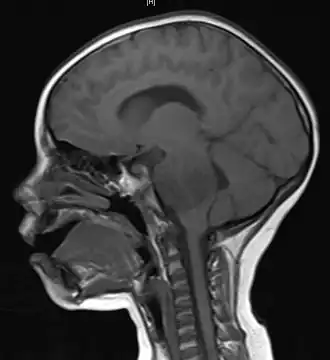

Resonancia magnética sagital en la que se observa un glioma en el tronco cerebral de un paciente de 4 años de edad. | ||